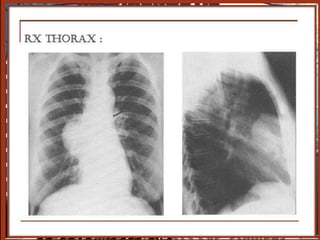

a) radiographie du thorax

La “masse”= aspect d’une opacité de forme, de dimension

et de siège très variable dans médiastin

On précisera

- le type : unique ou multiple, rond,

bossé ou polycyclique

- le siège: compartiment du médiastin

- l’homogénéité ou l’hétérogénéité de

l’opacité.(calcifications)

Opacité médiastinale

- homogène

- limite externe nette

- continue,

- convexe vers le poumon,

- se raccordant en pente douce

- avec le médiastin

- à limite interne

- Invisible(noyée ds le médiastin)